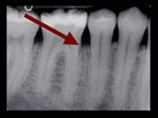

Zahnärztliches Röntgenbild mit Pfeil auf entzündetes Knochenareal an einer Zahnwurzel, Hinweis auf parodontale Erkrankung.

Röntgenaufnahme des Kiefers mit sichtbarem Knochenabbau bei fortgeschrittener Parodontitis.